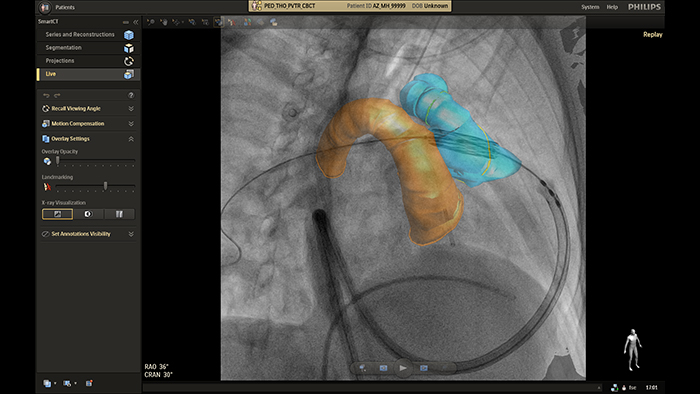

Orientação em tempo real do SmartCT